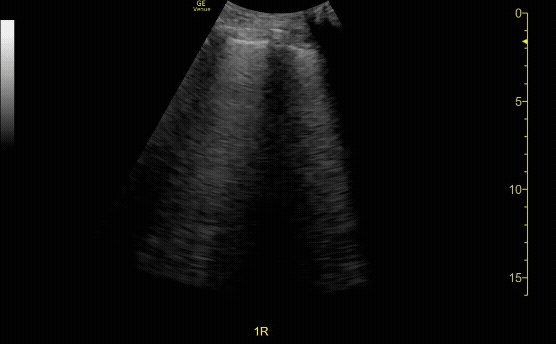

Ring Down Artifact: appears as a continuous, bright vertical echo extending deep to a gas bubble, caused by resonance of trapped air. B lines (seen here) in thoracic ultrasound are caused by this artifact and phenomenon.

c/o Kevin Boubouleix, MD